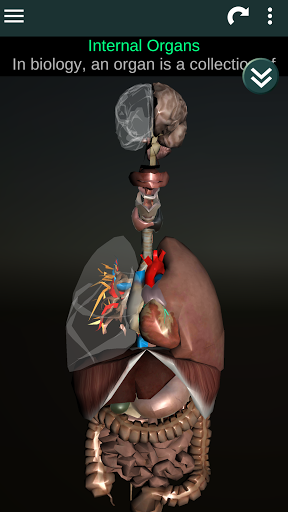

Internal Organs in 3D Anatomy لـ Vodafone Smart N9 Lite

(الأجهزة الداخلية في)

Internal Organs 3D Anatomy 3.4

يمكنك هنا تنزيل ملف حزمة تطبيق أندرويد "Internal Organs 3D Anatomy" الخاصة بجهازVodafone Smart N9 Lite مجانًا، نسخة ملف حزمة تطبيق أندرويد - 3.4 للتحميل على Vodafone Smart N9 Lite اضغط ببساطة على هذا الزر. إنه سهل وآمن. نحن نقدم فقط ملفات حزمة تطبيق أندرويد الأصلية. إذا انتهكت أية مواد موجودة في الموقع حقوقك قم بإبلاغنا من خلال